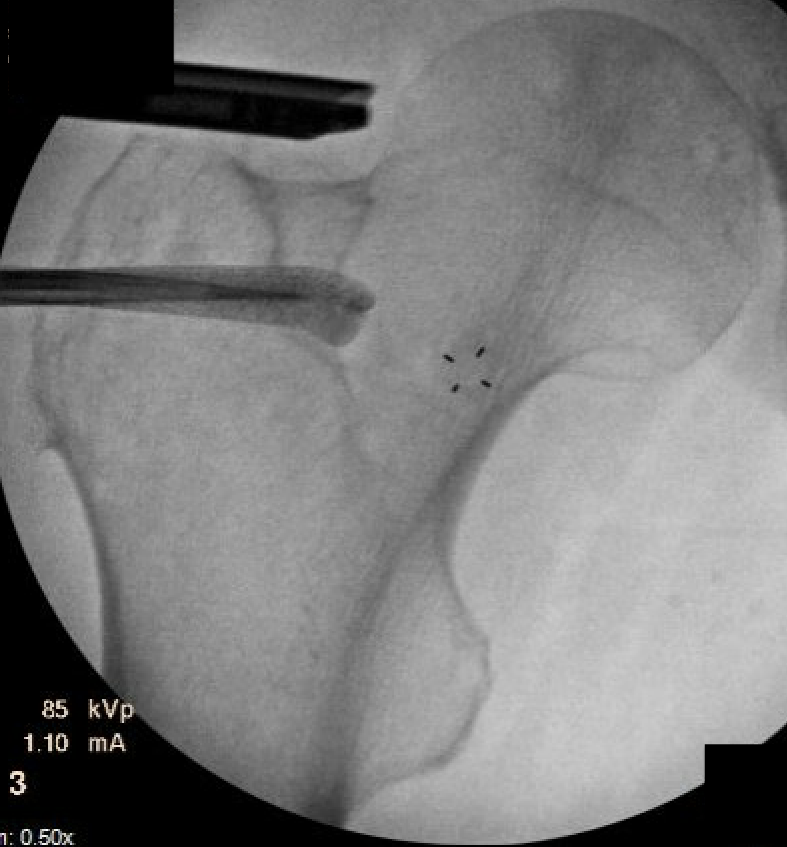

Injections

CT / Ultrasound guided local anesthetic and cortisone around quadratus

- diagnostic

- +-/ therapeutic